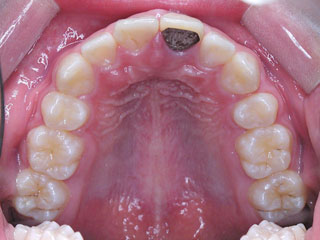

保定治療に移行してから3年半が経過しました。上の顎に生えてきた親不知は下の顎の奥歯と噛み合うようになりましたが、下の親不知は、斜めに埋まっていましたので、噛み合わせへの変化を防止するためにも早めに抜いて貰いました。矯正治療ではなるべく長期に渡って、管理を行いますが、2年3年と大きな変化が無く、緊密な噛み合わせが確保出来ていれば、将来的にも安定が期待出来ると思います。